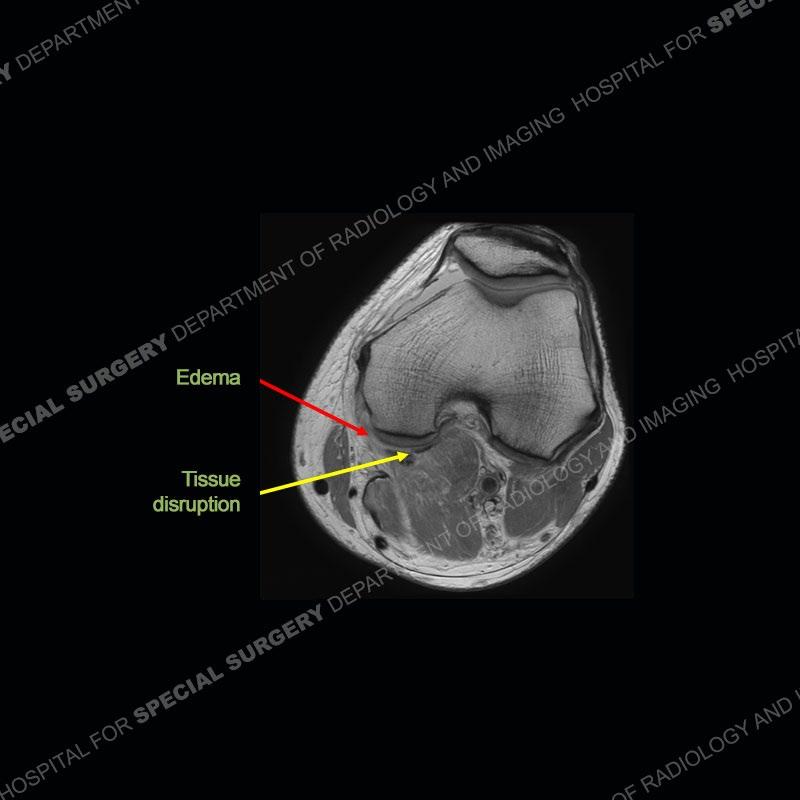

The radiographs show degenerative change of the medial compartment and a varus knee, but they are not germane to this case. No acute bony injury is present. The MRI shows edema of the posterior medial knee/soft tissue and a focal area of a partially disrupted low signal structure. The details are kept at a minimum in the findings of this case on purpose.

Fourth, use all imaging planes and different pulse sequences to make your diagnosis. The edema highlighted in this case can be seen as the obscuration of fat on the PD images but is much easier to perceive as the high signal on the IR pulse sequences. The actual disruption of the MHG myotendinous junction is only able to be seen on the axial images. On the sagittal and coronal images, we get a sense something is wrong but hard to be exact. Lastly, when you look at a study and something just seems off (as I would say the sagittal and coronal images do with that dark band of tissue posteriorly), listen to yourself and go through the study slowly and meticulously. Most of the time you will find you were right, and something indeed is present.